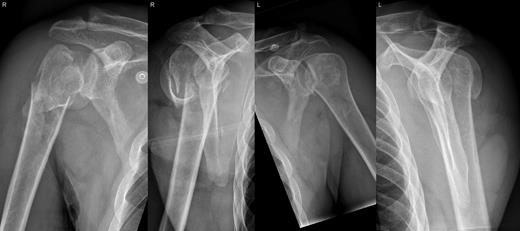

A 48-year-old patient was referred to a level I trauma center after the first incidence of an epileptic convulsion. The patient was alert and oriented with retrograde amnesia from the time of convulsion. Peripheral neurology was normal. The X-rays showed bilateral posterior shoulder dislocation with fractures of both humeral heads (Fig. 1). A CT of the head and both shoulders was performed to exclude intracerebral pathology and to achieve better demonstration of the shoulder fractures (Fig. 2). According to the AO fracture classification, he had a 11-C3.1 fracture on the left side and a 11-C3.3 fracture on the right side. The right side fracture was treated with a cementless hemiarthroplasty (OrTra®, Zimmer, Germany), while an open reduction and internal fixation (ORIF) with an angular stable plate (Philos®, Synthes, Germany) was performed on the left. Despite the high incidence for humeral head necrosis after ORIF in this fracture type, this option was chosen based on the young age of the patient. Postoperative X-rays and CT showed adequate positions of the implants (Fig. 3). The shoulders were immobilized in Gilchrist bandages followed by passive mobilization for the first 6 weeks by physiotherapy with a limitation for abduction and anteversion to 90°. There were no complications intraoperatively or in the first postoperative time. Patient was discharged after 8 days. Antiepileptic therapy was initiated with 5 mg clobazam and subsequent increasing doses over the following weeks. There were no more signs of epilepsy in the follow-up. A CT 4 months after operation showed dislocation of a fragment on the left side which was subsequently resected. At the 1-year postoperative review, the patient showed impingement of the left shoulder with abduction limited to 50° by both the plate and an osteophyte. Radiological assessment revealed signs of necrosis of the head. The plate was removed and the osteophyte resected. Eighteen months after injury, the left shoulder showed progressive avascular osetonecrosis of the head (Fig. 4) and after plate removal an inversed prosthetic replacement had to be performed (Fig. 5). At the last follow-up 3 years after injury, the patient was free of pain with a bilateral range of motion of 90° abduction and elevation.

Postoperative X-rays after hemiprothetic replacement on the right and angle stable plate osteosynthesis on the left side.